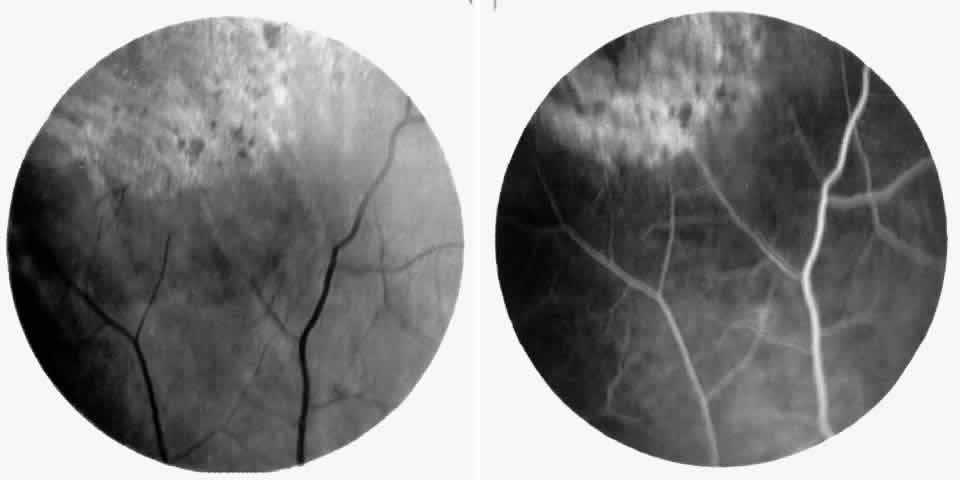

Choroidal Vascular Occlusions

Choroidal vascular occlusions may occur focally at the level of the choroidal precapillary arteriole or capillary bed (Elschnig's spots) or from posterior ciliary artery occlusion. Although focal precapillary arteriole occlusions have not been specifically identified with sickle cell disease, clinical and histopathologic evidence of spontaneous posterior ciliary artery occlusions have been reported in sickle cell disease.109,110 The findings are similar to those described following compression of the eye during general anesthesia and after heavy peripheral photocoagulation.111,112 In the acute phase, the occlusions appear as white, circumscribed, triangular patches at the level of the retinal pigment epithelium and outer retina. Over the following weeks, the white lesions fade and retinal pigment epithelial mottling develops (Fig. 15). Since patients with acute ciliary artery occlusions may be asymptomatic and the diagnosis is often based solely on the appearance of peripheral pigment mottling, the frequency of this complication remains uncertain.

Fig. 15. A 25-year-old man with homozygous sickle cell anemia and proliferative sickle retinopathy. A. Photograph demonstrating nonperfusion and wedge-shaped pigment mottling representing a choroidal infarction. B. Fluorescein angiogram demonstrating hyperfluorescence at the level of the retinal pigment epithelium.